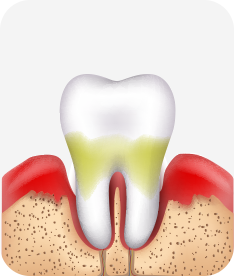

치은염 (초기~중기)

치아 주위의 잇몸이 붉게 부어 있으며, 칫솔질 등을 할 때 피가 남.

스케일링 주기의 조절이 필요할 수 있으며, 올바른 칫솔질을 시행하여야 함.

치주염 (중기~말기)

주기적으로 잇몸이 붓고 피가 나며, 욱씬하거나 우리한 통증이 나타남.

치주치료 및 정도에 따라 치주수술(잇몸수술)이 필요함. 향후 관리 정도에 따라 3~6개월 간격으로 내원하여 유지치료를 시행하여야 함.

치주염 (말기)

잇몸이 항상 부어 있으며, 이가

흔들리는 정도가 점점 심해짐.

치주치료가 필요하며, 정도에 따라 치아를 발치하여야 할 수 있음.